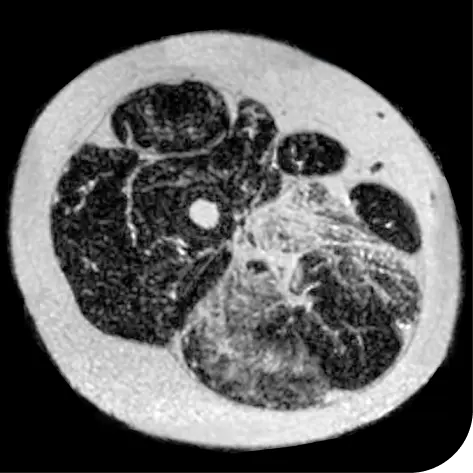

DUVYZAT also reduced how much new fat was in the muscle, a measurement of muscle loss

- Those who took DUVYZAT + steroids had 30% less new fat build-up in their muscles than those who were on steroids alone

In another follow-up analysis of the clinical trial (meaning it was not one of the main measures planned when the study began), researchers looked at individual people to see how much new fat was in the muscle. The images below represent results from 2 individual people from the study after 18 months. These results may not be the same for everyone.

How to read these images:

- Magnetic resonance spectroscopy (MRS) images can show the difference between muscle and fat in the body

- By taking images of the same patients 18 months apart, researchers can track the amount of new fat that is building up in the muscles

- The darker areas of the images represent muscle tissue and the white areas represent fat

After 18 months | |

Participant taking DUVYZAT + steroids |